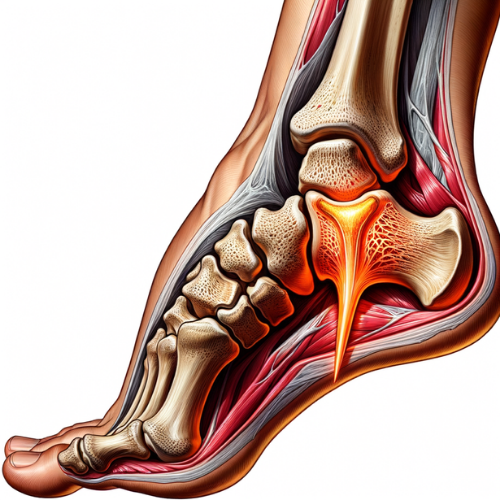

خار پاشنه چیست؟

خار پاشنه به تجمع کلسیم در قسمت زیرین استخوان پاشنه گفته میشود که به شکل یک زائده استخوانی ظاهر میشود. این زائده معمولاً در ناحیهای که رباطهای پا به استخوان پاشنه متصل میشوند، تشکیل میشود و میتواند باعث تحریک و التهاب بافتهای نرم اطراف شود. اگرچه این زائده استخوانی ممکن است تا حدود ۱.۲ سانتیمتر رشد کند، اما اندازه آن لزوماً تعیینکننده شدت درد نیست.

- پلانتار فاشئیت:

- التهاب و تحریک رباط پلانتار فاشیا (باند بافتی که از پاشنه تا انگشتان پا امتداد دارد) میتواند منجر به تشکیل خار پاشنه شود. این وضعیت معمولاً به دلیل فشار زیاد بر روی پاشنه و کف پا ایجاد میشود.

تشخیص خار پاشنه

تشخیص خار پاشنه معمولاً بر اساس علائم بالینی و معاینه فیزیکی توسط پزشک انجام میشود. پزشک ممکن است برای تایید تشخیص و ارزیابی شدت عارضه از روشهای تصویربرداری استفاده کند:

- رادیوگرافی (X-ray): رادیوگرافی معمولاً برای مشاهده زائده استخوانی (خار) در قسمت زیرین پاشنه استفاده میشود.

- MRI یا سونوگرافی: در موارد خاص، پزشک ممکن است از MRI یا سونوگرافی برای ارزیابی وضعیت بافتهای نرم و التهاب استفاده کند.